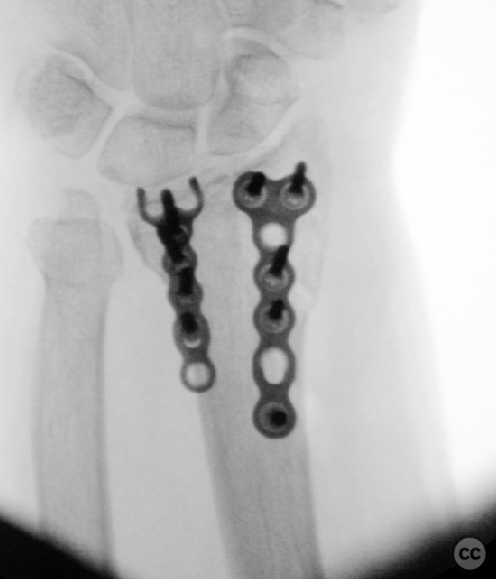

Clinical and radiological findings:  A 72-year-old female sustained a multifragmentary, dorsally displaced distal radius fracture after a fall down stairs. Initial reduction revealed a 180-degree flipped fragment of the volar ulnar articular margin, unreducible by closed means. There was no mention of associated neurovascular compromise or open injury. Radiographs and intraoperative fluoroscopy confirmed the presence of a multifragmentary intra-articular fracture (AO/OTA 23-C3), with a flipped volar ulnar fragment and radial styloid impaction. The distal radioulnar joint alignment was restored postoperatively.

Anatomical surgical approach:  A longitudinal incision was made over the flexor carpi radialis (FCR), zigzagging over the wrist crease. Subcutaneous dissection and incision of the FCR tendon sheath were performed, followed by transection of musculus pronator quadratus fibers along the radial border of the distal FCR. The FCR tendon was retracted ulnarly, and the antebrachial fascia incised. Musculus flexor pollicis longus was identified and retracted ulnarly. The pronator quadratus was incised along its radial border and the watershed line, then elevated subperiosteally to expose the distal radius. Extended distal release of the FCR allowed wide exposure of the ulnar aspect of the lunate facet and volar lip. The flipped volar ulnar fragment was de-rotated and provisionally fixed with a Kirschner wire. Ligamentotaxis for radial styloid reduction was achieved using Kirschner wires in the scaphoid and distal radius, with a wire spreader applied for distraction. Provisional fixation was achieved with multiple Kirschner wires. A mini-fragment T-plate, cut and shaped as a hook plate, was applied to the volar ulnar lip fragment, fixed with bicortical screws, and used to engage dorsal fragments. The radial styloid was addressed with a contoured T-plate, similarly fixed with bicortical locking screws. Final multiplanar fluoroscopy confirmed anatomical reduction and hardware placement.

The flipped volar ulnar articular margin fragment was irreducible by closed means due to capsular attachment and required direct open de-rotation and fixation. The impaction and proximal displacement of the radial styloid fragments were challenging due to persistent traction from musculus brachioradialis and scaphoid pressure; ligamentotaxis using Kirschner wire spreader over the scaphoid facilitated reduction. Fragment-specific fixation was necessary: a custom-shaped hook plate for the volar ulnar lip fragment provided stable fixation and prevented dorsal instability, while a separate T-plate addressed the radial styloid. Bicortical locking screws were used to secure both plates, with some screws engaging dorsal fragments from the volar side. Careful adaptation of pronator quadratus over hardware minimized risk of musculus flexor pollicis longus irritation. Additional suture stabilization of radiocarpal ligaments to pronator quadratus provided secondary ligamnetal support.

Orthopaedic implants used:   - 1.0 mm Kirschner wire (provisional fixation) - 1.8 mm Kirschner wire (scaphoid traction) - 2.0 mm Stryker mini fragment T-plate (cut/shaped as hook plate) - 2.4 mm T-plate (radial styloid fixation)